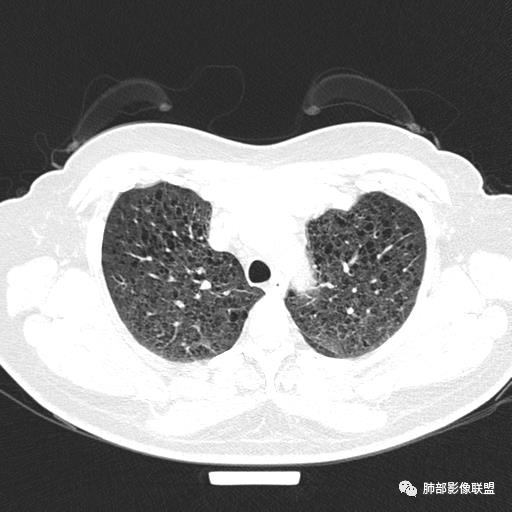

中年女性,不吸烟

双肺弥漫囊腔,累及肋膈角,囊腔形态相对规则单一。

CT平扫示双肺弥漫分布大小不等囊状薄壁透光区,无内、中、外带分布差异,间质稍示增厚。拟LAM

中年女性育龄期妇女,咳嗽气喘,无吸烟史,有苯吸入史。影像:双肺弥漫均匀小囊腔,无明显分布优势,囊腔形态欠规则,壁薄,部分囊腔边缘血管征,伴双肺弥漫磨玻璃影,无结节,考虑lam,鉴别苯中毒肺损伤,囊腔多有分布优势,小叶中心分布为主,形态规整等

女,46,活动性气喘1年。苯吸入史半年。胸部CT:两肺弥漫囊腔,上至肺尖,下至肋膈角,形态类似小囊腔。考虑:LAM,鉴别LIP,BHD,PLCH等。

双肺弥漫大小不一薄壁含气囊腔,囊间肺组织正常,正常肺背景,肺尖肺底受累;青年女性,气喘,支持LAM

双肺多发大小相近的囊状影,分布趋势趋于一致,中年女性,考虑LAM。部分囊内见血管及分隔影,小叶中心性肺气肿代排

CT表现:双肺弥漫大小不等的薄壁囊腔,囊壁<2mm,外形规则,血管影多位于囊腔周围,囊腔之间肺组织正常,随着疾病进展到晚期,囊腔变大、增多,不可胜数,囊腔可融合成较大的囊,与肺气肿相似,形成间质性肺纤维化。部分病例可出现结节影。